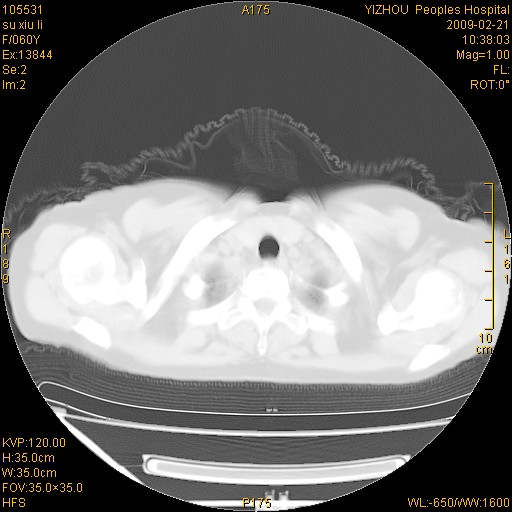

标题: CT18259:两肺间质纤维化?

女,60岁,反复咳嗽1月。

两肺支扩,以肺为著合并双肺较广范纤维化病变。建议除外结核等病变。

符合间质感染,部分纤维化表现

特发性间质纤维化

特发性间质纤维化伴支扩!